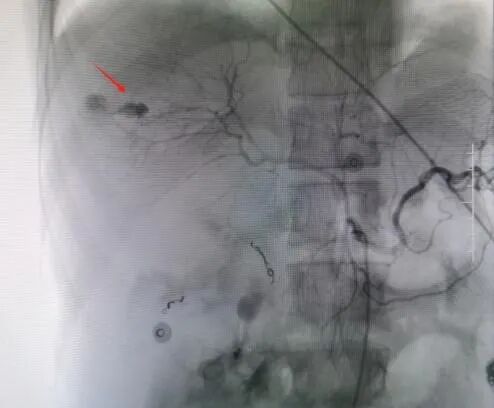

术后DSA造影图

救治方案明确后,患者立即被推入了手术室,在邓文军总监的指挥下,一场惊心动魄、紧张有序的手术开始了。各专科主任严阵以待,在院待命,随时做好开腹手术准备。介入手术由影像中心副主任兼介入组组长吴继雄主任医师亲自主刀,手术过程顺利,术中造影找到右肾脏有几处明显的活动性出血点,肝脏也有两处活动性出血点,给予及时栓塞止血后,再次造影无明显出血。整个手术仅约一个小时,刀口仅针眼大小,术中病人情况稳定,失血量不到10ml,患者成功脱离生命危险,术后被送入ICU密切观察诊治。病情平稳后转入普通病房,经过后续治疗目前该患者已经平安出院,出院时状态良好已经能自行走路。